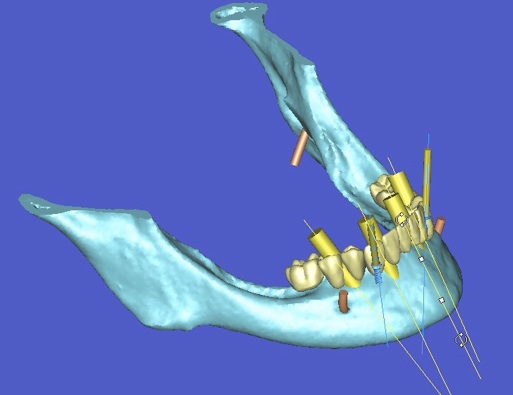

l’informatique au service de l’implantologie

La société Materialise a développé un logiciel SIMPLANT qui permet de simuler la position des futurs implants et de les transférer en bouche à l’aide d’un guide chirurgical.